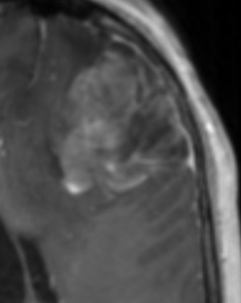

Glioblastome

Decouverte fortuite aux urgences, Confirmé a la patho

Decouverte fortuite aux urgences, Confirmé a la patho